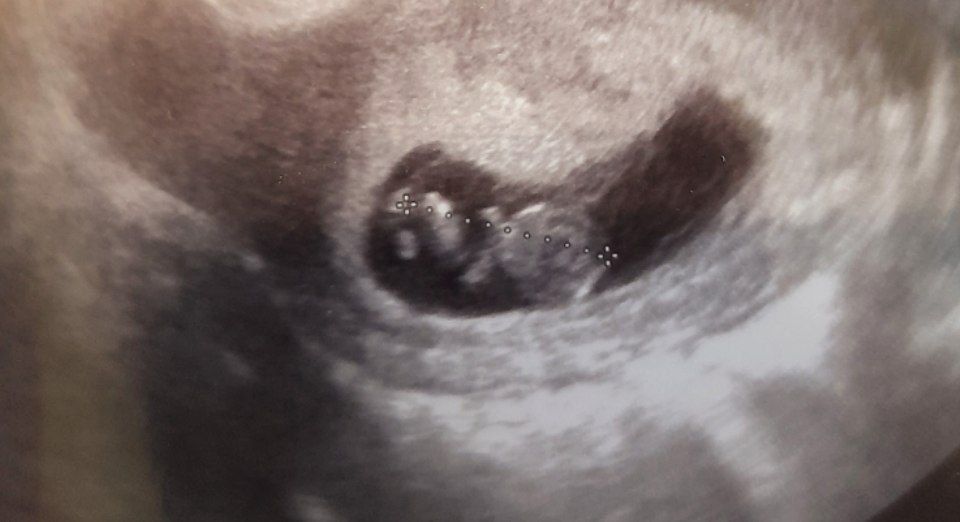

Вот и прошла 1/4 беременности, даже не верится. На узи уже целый человечек, с ручками, ножками, пальчиками, ребятёнок оказался очень активным, сняла даже видео на память :) Расплакалась опять😆 Пальчик уже сосал) Расположение сказали "королевское", по передней стенке у дна матки😏 Квартиру человек тоже выбрал себе не маленькую, яйцо больше в два раза😆 ПЯ на 10+1, а ребёнок ровно на 9 недель по всем показателям😊 Жду с нетерпением 1 скрининг (24 числа)😍

ПЯ - 53,8мм

КТР - 25,1мм

ЖМ - 6,9мм

ЧСС - 187 уд/мин